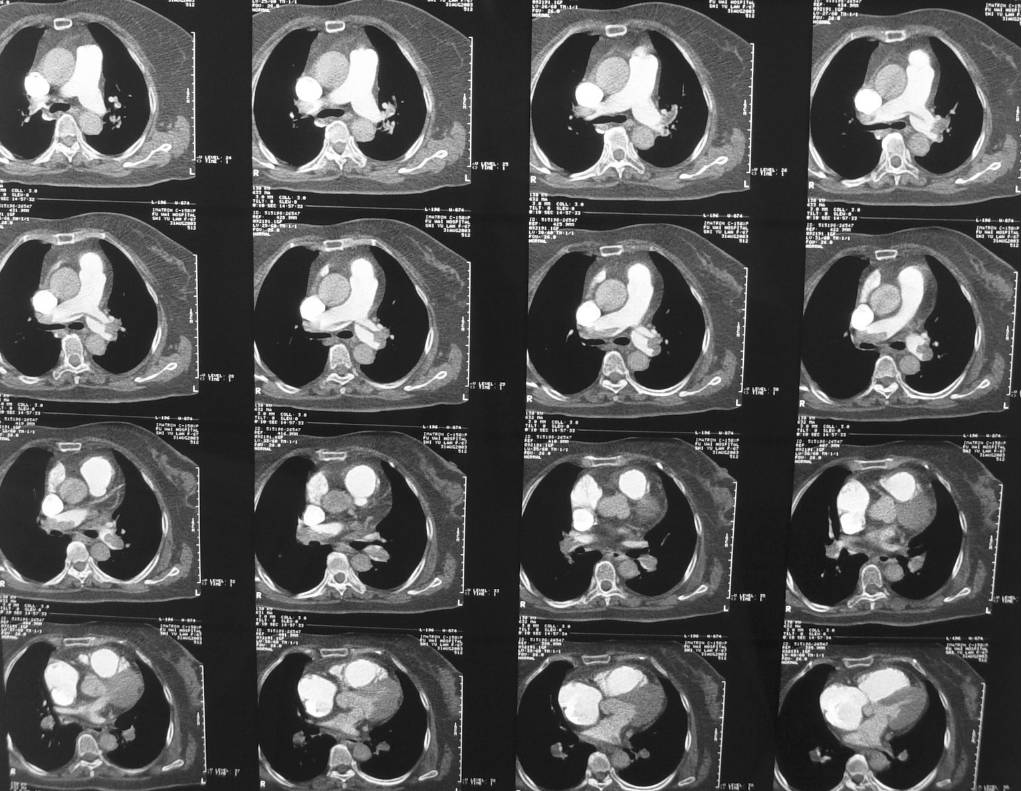

2.增强CT肺动脉造影

4.核素肺通气/灌注扫描+下肢深静脉显像

5.肺动脉造影和下肢静脉造影